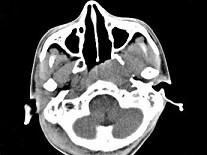

问题 男,17岁,自诉鼻涕中带血3个月,伴耳闷、听力减退,无发热。如图所示鼻咽部病灶最可能的诊断为 ( )

选项 A、小唾液腺混合瘤 B、鼻咽部淋巴组织增生 C、鼻咽部恶性淋巴瘤 D、鼻咽癌 E、咽旁脓肿

答案 D